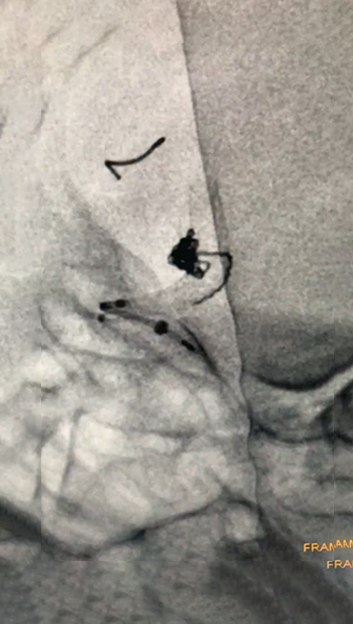

4.1)

造影显示动脉瘤致密栓塞

随访影像

术后一月复查的影像,动脉瘤未见复发及残留,载瘤动脉修复满意。